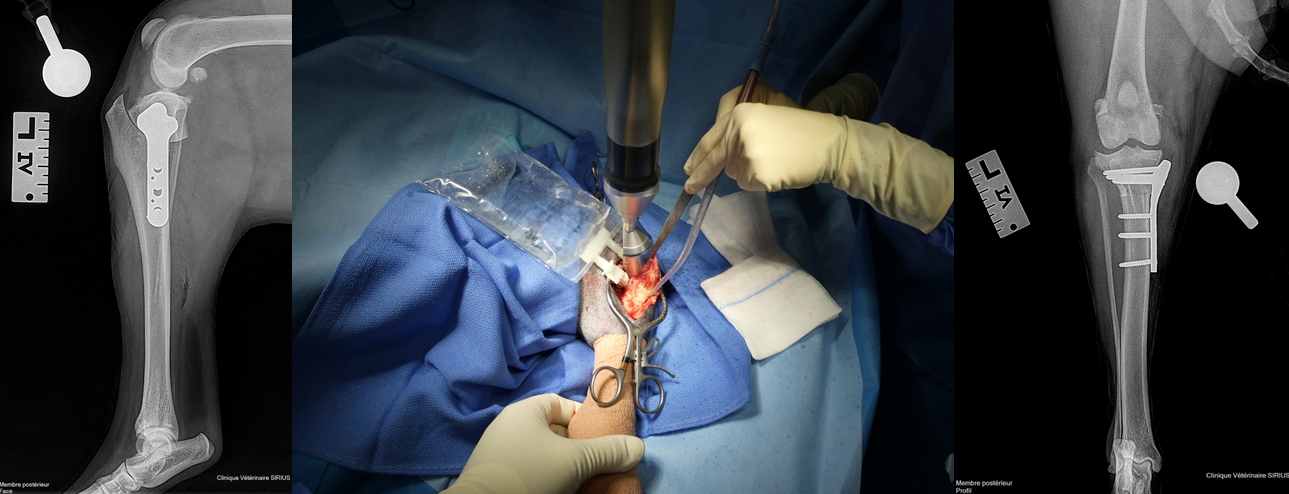

Réalisation d’une TPLO sur un chien atteint de rupture du ligament croisé crânial.